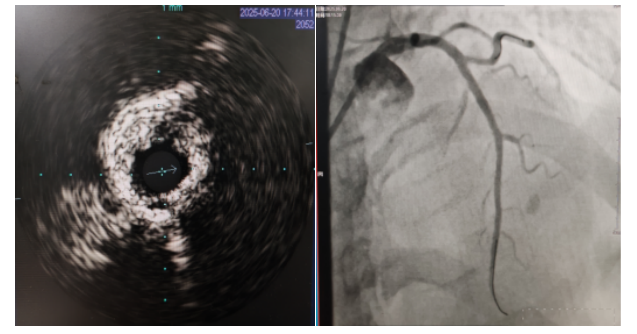

術(shù)中,趙慶禧主任醫(yī)師、雷剛副主任醫(yī)師運(yùn)用IVUS血管內(nèi)超聲技術(shù)評(píng)估,發(fā)現(xiàn)患者前降支、對(duì)角支0.1.1型真性分叉病變,前降支近中段嚴(yán)重鈣化、成角并99%狹窄,對(duì)角支近段嚴(yán)重鈣化并99%狹窄,傳統(tǒng)冠狀動(dòng)脈旋磨術(shù)容易引起冠狀動(dòng)脈穿孔,決定采用沖擊波球囊技術(shù)即血管內(nèi)沖擊波鈣化碎裂術(shù)對(duì)患者嚴(yán)重鈣化的血管進(jìn)行介入治療。通過(guò)球囊低壓擴(kuò)張,向血管病變處發(fā)射非聚焦、低能量、脈沖式的沖擊波,對(duì)前降支及對(duì)角支進(jìn)行了連續(xù)5個(gè)周期沖擊波脈沖治療,安全地碎裂淺、深層鈣化,原本看似堅(jiān)不可摧的環(huán)形鈣化區(qū)逐漸顯現(xiàn)出了裂痕,多處關(guān)鍵位置發(fā)生了斷裂,充分預(yù)處理后于前降支近中段串聯(lián)植入支架3枚,對(duì)角支植入藥物球囊,術(shù)后造影見血管病變處狹窄完全消失,支架膨脹完全,貼壁良好,各項(xiàng)生命體征平穩(wěn),手術(shù)非常成功,患者返回心血管內(nèi)科病房繼續(xù)治療,并于4天后順利出院。